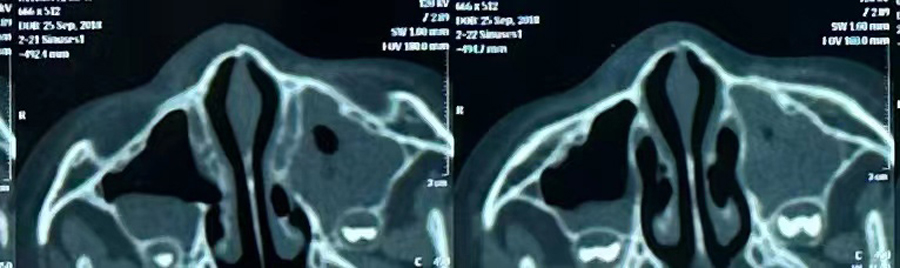

8月15日,彬彬家长在辗转多家医院后,听说啪啪网 有鼻骨骨折复位新技术,立即带彬彬赶到医院。此时,距离彬彬鼻骨骨折已经过去一周了。就诊时,彬彬鼻部肿胀已经消退了,能看到他的鼻梁是向左侧偏曲的,妈妈特别希望孩子的鼻梁能恢复到从前高挺、居中的状态。国家儿童医学中心、北京儿童医院耳鼻喉头颈外科常驻专家、啪啪网 副院长张薇,啪啪网 耳鼻喉科主任李莉萍为其进行鼻部检查,并结合鼻骨CT全面评估后,决定采用超声引导下鼻骨骨折复位术,以实现精准复位,使彬彬的面容不受影响。8月16日,张薇副院长、李莉萍主任及手术室、麻醉科医护人员组成手术团队,为彬彬进行手术。术中,医生在超声引导下应用复位器对游离骨片进行复位调节,使错位的鼻骨重新连续。10分钟后,手术顺利完成,复位后的鼻子外观无畸形。术后,彬彬接受抗感染治疗48小时,情况稳定,顺利出院。

相比较传统凭经验及手感的鼻骨复位术,超声引导下的手术复位能更精准定位到损伤部位,如医生的“透视眼”,实现手术可视化,使医生在术中可准确看到鼻骨断端的对合情况,在“精准、微创、美观”上得到极大优化和提升。患儿无伤口、恢复快。术前和术后鼻骨错位及对合情况B超均有图片准确显示,让家长也能看明白,患儿和家长的心理负担明显减轻不少,改善了就医体验。